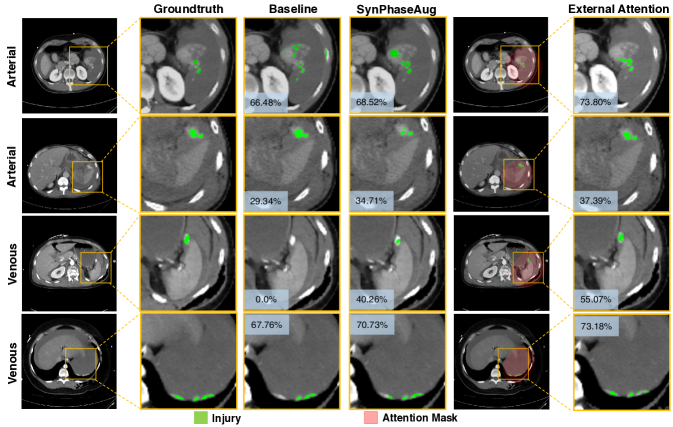

Refer to caption

Figure 4: Qualitative comparison. Synthetic phase augmentation already yields a performance improvement, while external attention can further enhance the segmentation accuracy. The improvement can be witnessed for both arterial and venous phases. The generated attention mask well aligns with the region-of-interest.

Our experimental results also validate this intuition, i.e., synthetic phase augmentation without self-learning (indicated by SynPhaseAug (w/o self-learning) in Table 2) results in performance degradation as large as 2.36%percent2.362.36\% on the arterial phase in segmentation accuracy. With self-learning, the performance improvement compared with Joint can be more than 4%percent44\% in terms of average DSC, boosting the performance on the venous and the arterial phase from 47.06%percent47.0647.06\% and 50.05%percent50.0550.05\% to 51.36%percent51.3651.36\% and 54.55%percent54.5554.55\% respectively. We have also provided the performance comparison in boxplot (see Fig. 5(2)). This large performance improvement suggests that the joint training with synthetic phase augmentation in a self-learning manner not only enables an augmented training set, but also allows a more thorough knowledge integration from both phases. The benefits of synthetic phase augmentation are also demonstrated in Fig. 4.

As aforementioned, compared to Joint, i.e., directly training with multi-phase images, training with additional synthetic phases (SynPhaseAug) already suggests large benefits. Nevertheless, from Table 2, we observe exploiting external attention can further lead to a performance gain of 3.41%percent3.413.41\% and 3.99%percent3.993.99\% on each phase compared with SynPhaseAug. The performance comparison in boxplot (see Fig. 5(2)) further suggests the significance of the improvement. We also demonstrate the effectiveness of the proposed external attention in a set of qualitative examples, e.g., as shown in Fig. 4, the computed attention masks are well aligned with the region-of-interest, which effectively reduces the irrelevant responses from the background region during the learning process. Last but not the least, it is also worth mentioning that even without synthetic phase augmentation, pure external attention (indicated by External Attention (w/o SynPhaseAug) in Table 2) also achieves superior results than Joint by a large margin of 5.83%percent5.835.83\% and 5.96%percent5.965.96\% in the arterial and venous phase, respectively. The generalization of pure attention is also well justified in Sec. 4.4 and Sec. 4.5.